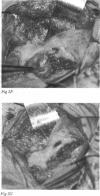

Periorbital dermoid cysts should be removed because they commonly leak their irritant contents into the surrounding tissues. The underlying bone may, however, be involved in patients with dermoid cysts at the outer canthus. Computed tomography studies of 70 patients (43 men and 27 women, aged 30 months to 63 years, mean 29 years) with proved dermoid cysts of this type were reviewed. The lesion was always unilateral; 34 were on the left. The bone of the lateral wall and superotemporal angle of the orbit showed the following abnormalities, often in combination: pressure erosion in 61 cases and an otherwise abnormal shape, probably developmental, in 55; the dermoid cyst entered a tunnel or canal through the lateral wall in 24; a blind pit or crater in 15; and a cleft in 20; many patients also showed abnormal bone texture. These findings are extremely important for planning adequate surgery, and indicate that bony involvement is much more frequent than previously appreciated.